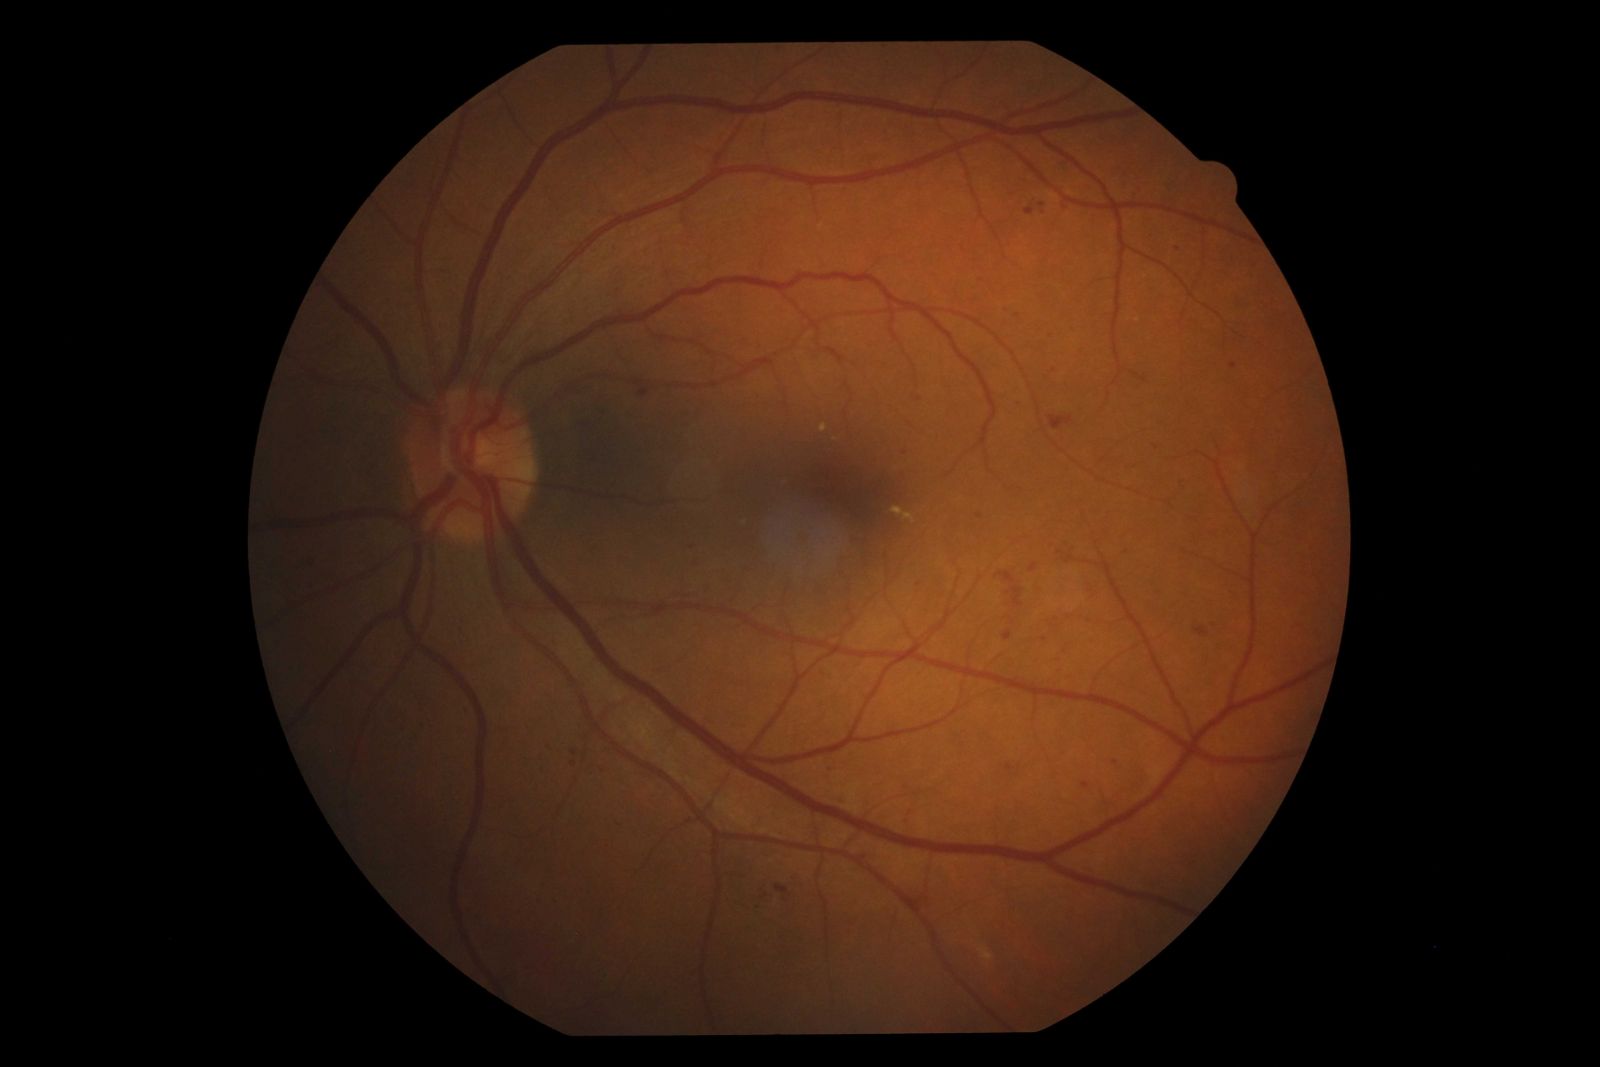

Contudo, independente do tempo de doença, quando o diabetes não esta controlado, a hiperglicemia desencadeia várias alterações no organismo, como aumento do fator de crescimento endotelial vascular (VEGF), danos na estrutura do DNA e de outros componentes celulares e da inflamação crônica. Essas alterações lesam os vasos sanguíneos e aumentam a permeabilidade vascular da retina, o que pode levar ainda à formação do edema macular diabético (figura abaixo).

Edema macular diabético visualizado em exame de OCT.

Na retinopatia diabética, a principal causa de baixa acuidade visual é o edema macular, acometendo cerca de 30% dos pacientes com mais de 20 anos de doença.